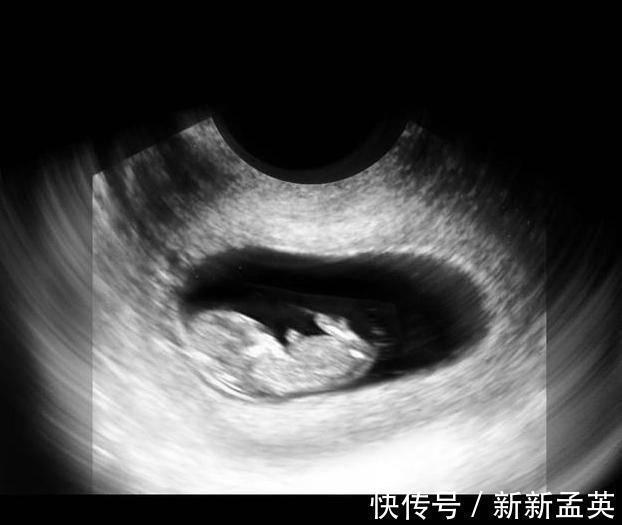

此时的宝宝可以叫做胎宝宝了,因为它已经具备很多人类的特征了,他的各个器官、肌肉和神经系统已经发育的产不多了,顾家也开始越来越坚固,从图片上看,宝宝就是迷你型的胎儿,他的各个器官开始工作了。